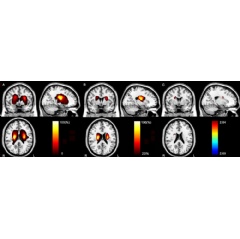

To investigate the mechanisms underlying attention deficit in chronic subcortical stroke, Dr. Yu and colleagues combined voxel-based lesion-symptom mapping (VLSM) and diffusion tensor tractography (DTT) in 49 patients (32 men and 17 women between the ages of 40 and 71) after subcortical stroke and 52 control patients (30 men and 22 women, age 40-68). VLSM is a method of analyzing relationships between tissue damage and behavioral deficits, and DTT is an MRI technique that allows for 3-D visualization of specific white matter tracts in the brain.

A modified version of the attention network test was used to assess visual attention function. VLSM was used to identify lesion locations related to attention deficit in the stroke patients. Then DTT was used to determine the responsible impaired brain connections at the chronic stage (- 6 months post-stroke).

The results showed that compared to the controls, patients with chronic stroke exhibited prolonged reaction time during the attention task. VLSM revealed that having an acute stroke lesion in the right caudate nucleus and nearby white matter was correlated to the prolonged reaction time. DTT showed that the responsible lesion was located in the right thalamic- and caudate-prefrontal pathways in controls.

The right brain damage subgroup had significantly decreased fractional anisotropy (FA) in these pathways, which were correlated with the prolonged reaction time. FA provides a way to measure diffusion occurring within a region of the brain. FA is typically higher in brain regions of high organization. Reductions in FA have been previously associated with advancing age and in cases of cognitive impairment.